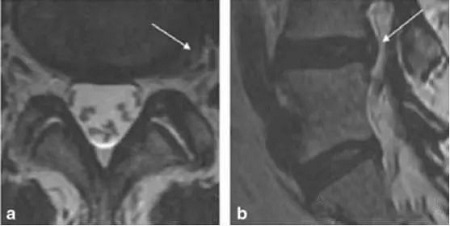

紐約spicial surgery 醫(yī)院的Gregory Lutz醫(yī)生報道了使用椎間盤內(nèi)PRP注射治療椎間盤退變的案例。患者是一位54歲的女性,嚴(yán)重的慢性腰痛,L4放射痛,L4-5椎間盤偏左側(cè)突出,接受過物理治療、非甾體類抗炎藥和介入治療,效果都不佳,2年后她接受了L3-4和L4-5椎間盤造影,發(fā)現(xiàn)L3-4正常,而L4-5誘發(fā)疼痛并發(fā)現(xiàn)纖維環(huán)裂隙?;颊呓邮芰薒4-5椎間盤內(nèi)注射PRP1.5ml治療,4周后疼痛幾乎完全緩解。18個月的隨訪疼痛和功能恢復(fù)非常滿意。

MRI示血小板注射前L4-5間盤膨出,箭頭示高密度區(qū)